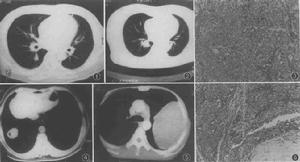

3、核素掃描:核素掃描用於臨床類癌的定位診斷,可檢出B超和CT不能顯示的微小病灶,其陽性率達80%~90%。放射標記的生長抑素類似物有助於確定腫瘤的位置和侵犯深度。

4、其他檢查:B超、CT、磁共振成像檢查對肝臟原發或轉移性癌診斷有指導意義。CT很少能夠發現原發胃類癌,僅有助於判斷是否有淋巴結和肝臟轉移。B超引導下肝穿刺或腹腔腫塊穿刺活檢,可幫助明確診斷而腔內B超或超聲內鏡檢查可同時對腫瘤大小、組織侵犯深度淋巴結有無轉移作出診斷。